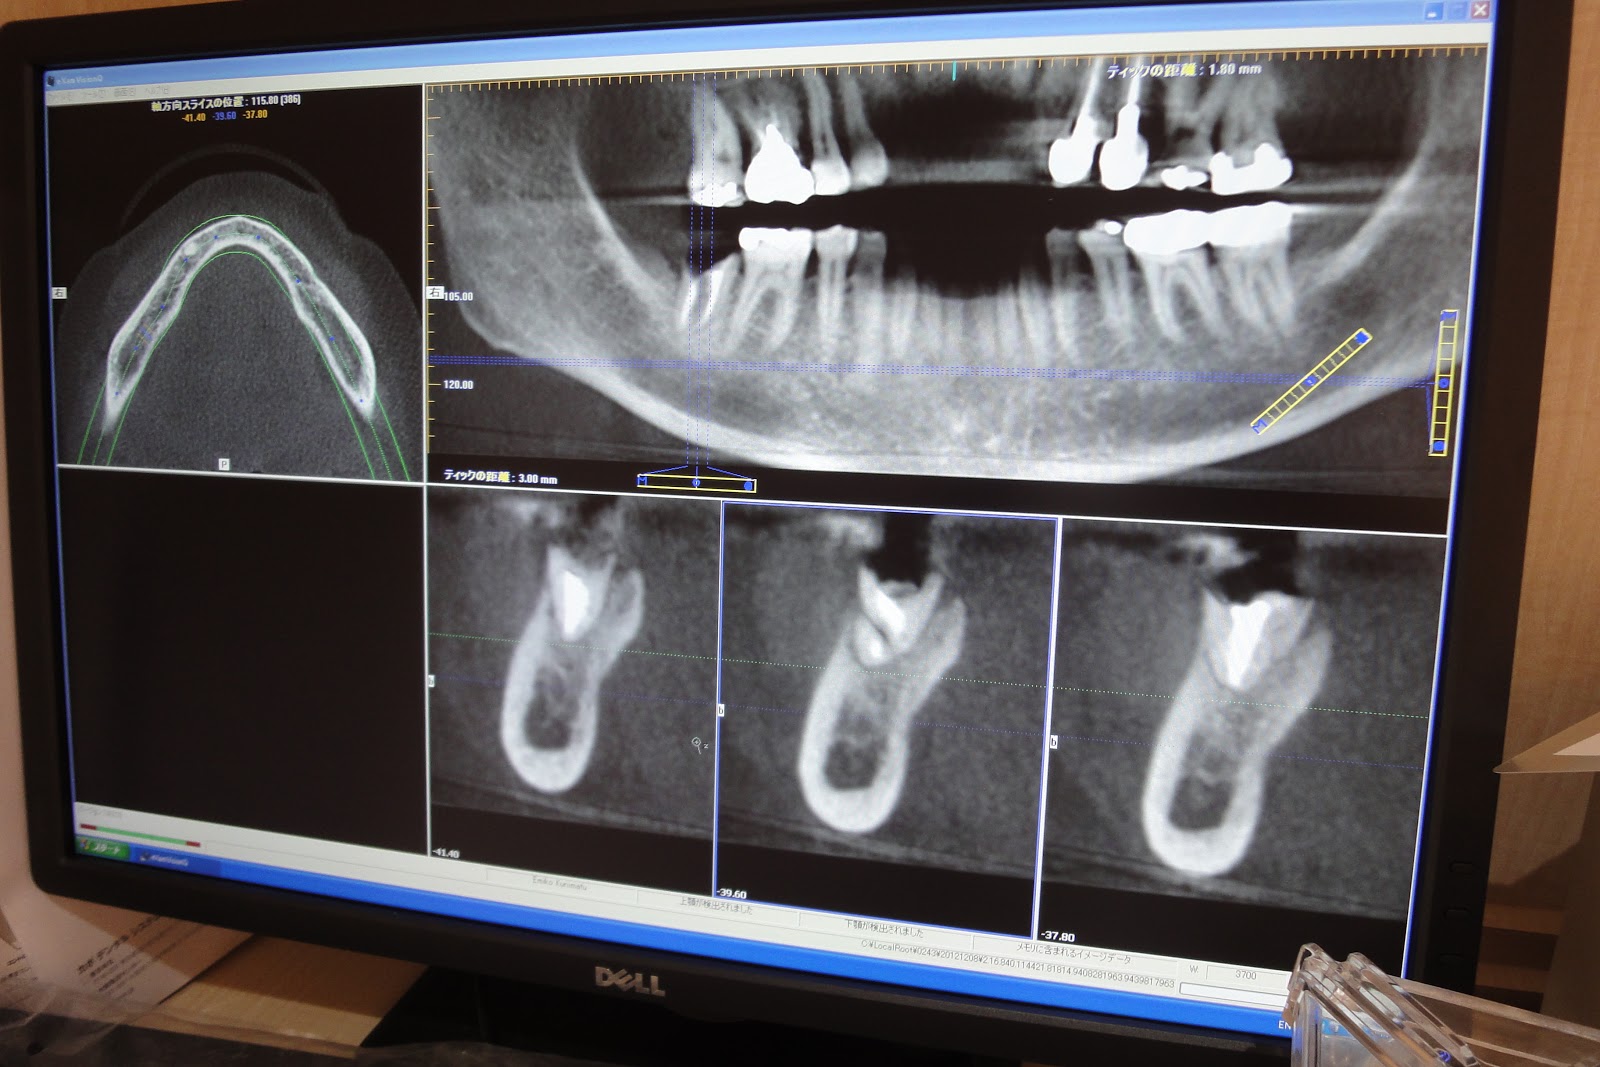

CTの撮影や読影ソフトの扱いもすべて頼りっぱなしです。

く、止む無くインプラントをお奨めしました。OKをいただき、早速

CTの出番です。

他に、もうお一人CTを撮影しました。この患者さんは来年にインプ

ラントをすることにしました。

結果としては、右下7は根も破折していることが分かりました。